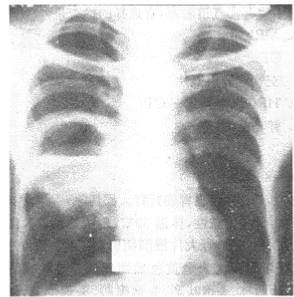

(70-71题共用题干)阅读胸片

病灶部位A.右肺下野B.右肺上野C.右肺中野D.左肺E.纵隔

C